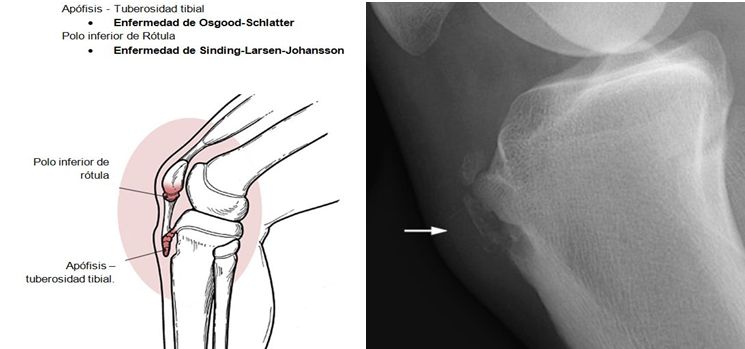

Alguna de ellas son: la enfermedad de Sinding-Larsen-Johansson, la enfermedad de Osgood-Schlatter, y la enfermedad de Sever; son osteocondrosis en las apófisis del poloinferior de la rótula, la tibia proximal, y el calcáneo, respectivamente.

Apofisitisde la rodilla

Es una entidad que produce dolor en la región anterior de la rodilla  (tuberosidad tibial), conocida como enfermedad de Osgood-Schlatter (EOS).  La condición, es un resultado de una tracción que ocurre en la tuberosidad tibial a causa del tirón del grupo muscular de los cuádriceps a través del tendón de la rótula.

Actualmente es ampliamente aceptado que la EOS es una tracción del tubérculo tibial debido a esfuerzos repetitivos, y avulsión crónica del centro de osificación secundario de la tuberosidad tibial. El esfuerzo repetitivo es un fuerte tirón del músculo cuádriceps producida durante las actividades deportivas. La avulsión de la tuberosidad tibial puede ocurrir en la fase pre-osificación, o con el centro de osificación secundaria ya osificado.

Esta apofisitis por tracción se desarrolla debido a la fuerza del tendón rotuliano en el polo inferior de la rótula. A diferencia de OSD, SLJ parece tener una predilección por los varones más que por las mujeres, y se observa en adolescentes activas entre las edades de 10 y 13 años. Debido a su madurez esquelética más temprana, las mujeres se ven afectadas a una edad más joven en comparación con los varones.

El síndrome de Sinding-Larsen-Johansson tiene una patogenia similar a la de la enfermedad de Osgood-Schlatter y los dos trastornos a veces se producen al mismo tiempo. El síndrome de Sinding-Larsen-Johansson es causado por el aumento de la tensión y de presión, debido a la tracción repetitiva por el tendón rotuliano en el polo inferior de la rótula (todavía en parte cartilaginosa en adolescentes) durante la contracción de los músculos cuádriceps.